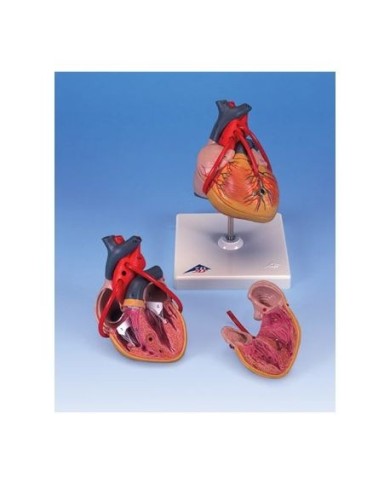

Kit composto da 3 modelli

Su Base, staccabile

Con scheda descrittiva dettagliata

Modello di cuore di alta qualità scomponibile in 5 parti

Modello di cuore di alta qualità scomponibile in 5 parti

La parete anteriore del cuore è staccabile per poter vedere i ventricoli.